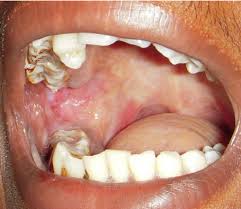

1. Buccal carcinoma commonly presents as a slow-growing mass on the buccal mucosa.

2. Small lesions tend to be asymptomatic and are often noted incidentally on dental examination.

3. Pain commonly occurs as the lesion enlarges and ulceration develops.

22. The lesion often has 1 of 3 morphologic types:

– Exophytic – The exophytic type is the most common, appearing as a papillary mass that becomes ulcerated when large.

– Ulceroinfiltrative – The ulceroinfiltrative variety appears as an ulcer that penetrates deep into the underlying structures, with surrounding induration.

– Verrucous – Verrucous carcinomas are uncommon variants of oral-cavity carcinomas; among these, the buccal mucosa is the most common site. These lesions appear as papillary masses, and keratinization gives them a whitish appearance.